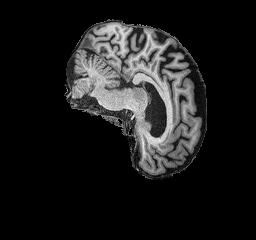

Figure 4: AD brain example